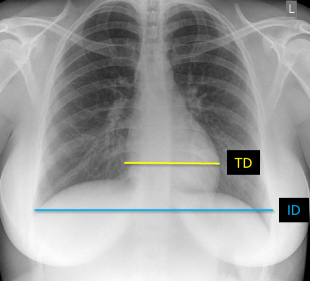

Q what is the name of this measurement? and what is the average + range?

A: Cardiothoracic Ratio

assesses the ratio of the transverse diameter of the heart to the internal diameter of the thoracic cage. The average is 45%, with a range of 39-50%.